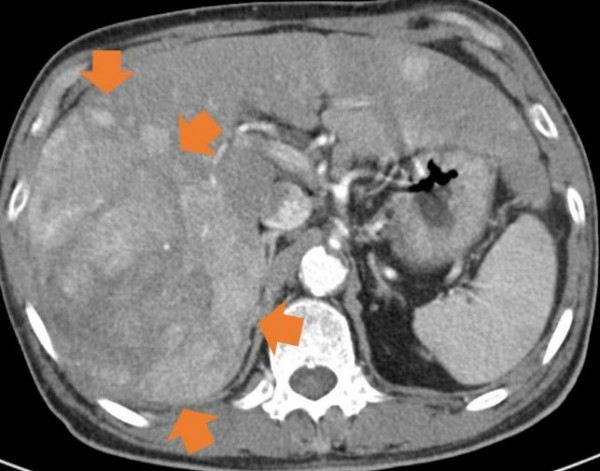

[오행생식 김미자 기자] 28일 국민건강보험공단이 건강보험 진료데이터를 활용해 2017년부터 2021년까지 간세포암(사진 1,2))’ 질환에 대해 분석한 결과 진료인원은 201759,040명에서 202164,525명으로 5,485(9.3%)이 증가하였고, 연평균 증가율은 2.2%로 나타났다.

사진1: 초기 간세포암, 사진 2:  진행된  간세포암 사진